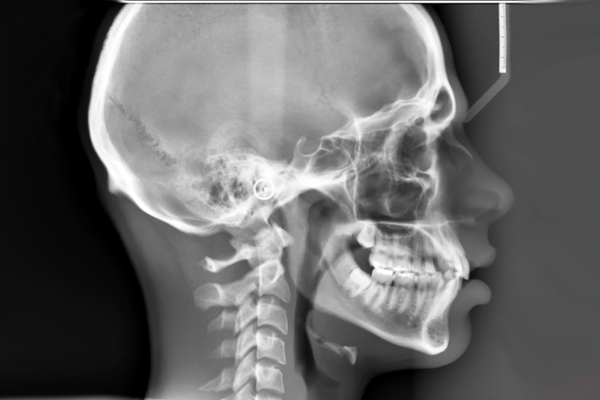

Uma documentação ortodôntica completa (exame pré-tratamento) inclui um conjunto de imagens radiográficas, fotografias e modelos virtuais ou físicos para o diagnóstico e planejamento de tratamentos como aparelhos ortodônticos.

Uma radiografia panorâmica (ou ortopantomografia) fornece uma imagem bidimensional (2D) ampla e única que abrange toda a estrutura bucomaxilofacial. Ela é fundamental para o diagnóstico geral e planejamento de tratamentos, mostrando de uma só vez os dentes, maxilares e articulações.